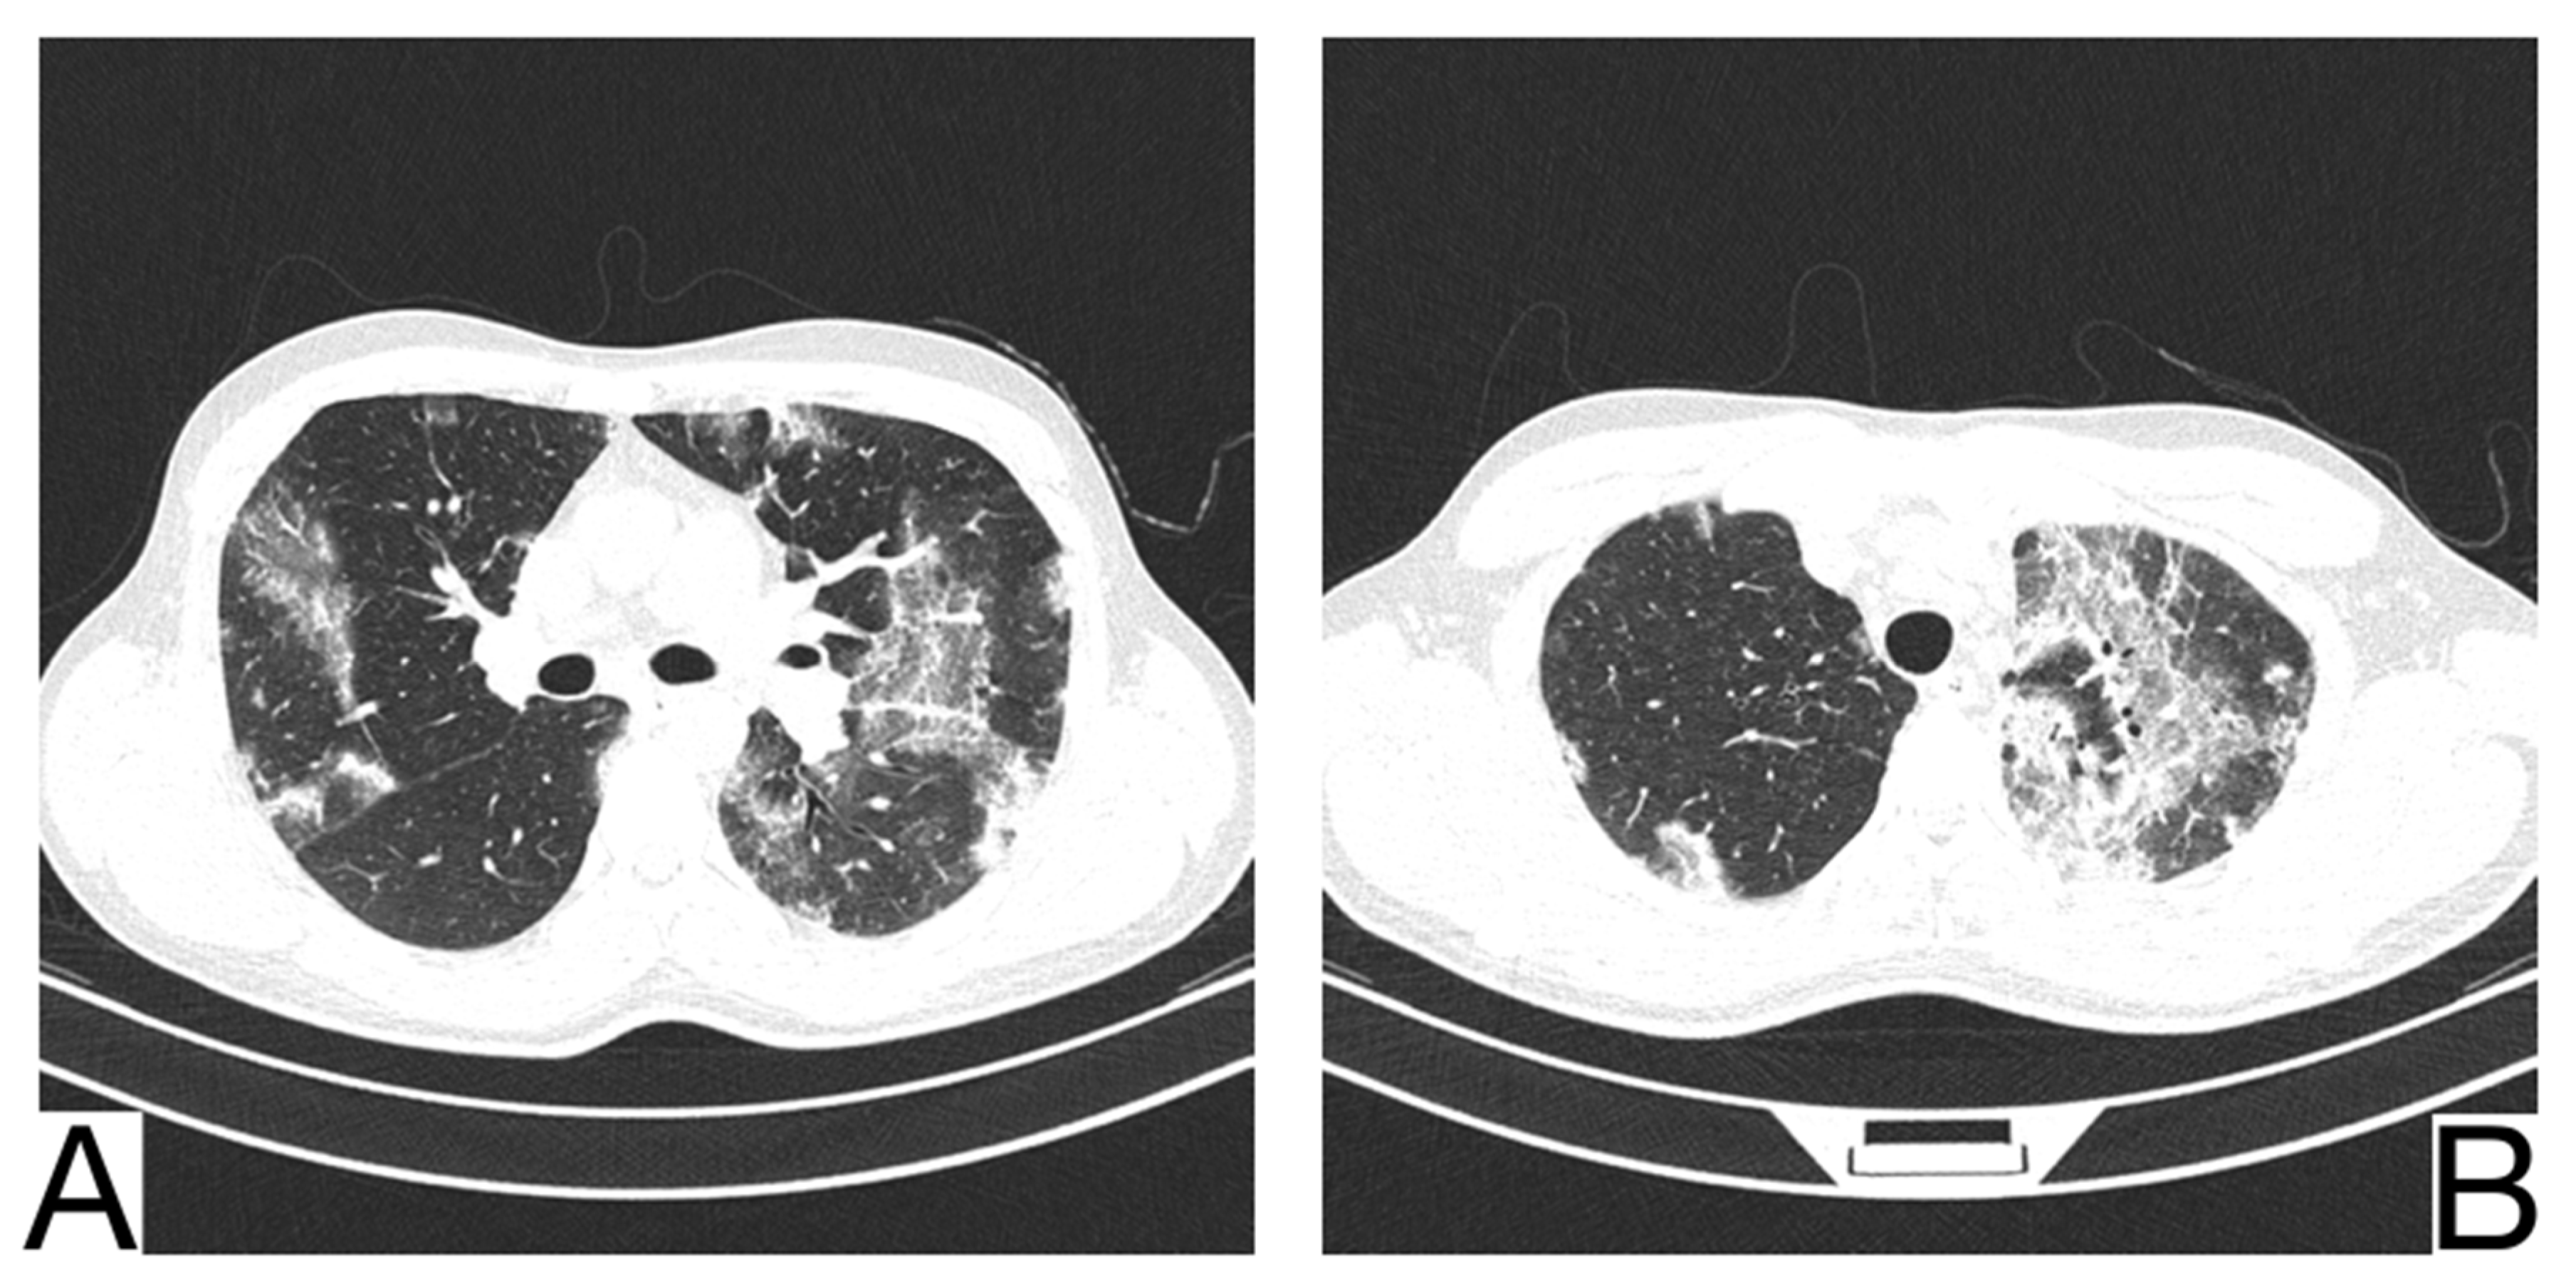

10.1. Bacterial Pneumonia

10.3. Pneumocystis Pneumonia